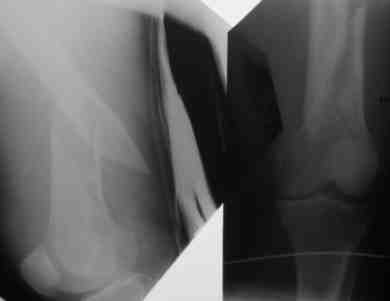

Попутно, разрешите поделится опытом закрытого ретроградного синтеза бедра. Внедрение тяжелая штука, пости года 2 прошло со времени обучения методике. Использовать/убедить использовать дистрактор на бедре/голени удавалось редко. Отлично дистрактор прижился на плече. Зав. отделением не знал точного плана операции(поэтому не смог помешать).Стокнулись со следующей проблемой - при попытке устранить ротацию теряли длину, при дистракиции получали ротацию, при чем при ротации телескопы очень плотно давят на бедро. Больная с ожирением, на ощупь проводили спицу проксимальной опоры, пульсацию бедренной артерии для ориентира определить не возможно. Проксимально латеральный телескоп все время оказывался длиннее, чем надо, меняли его положение.Не смотря на все это, считаю, без дистрактора данная операция заркрыто не возможна , особенно в наших условиях.

Успешный опыт пользвания дистрактором есть(я сам видел, не видел бы- бросил бы попытки пользования дистрактором). Пожалуйста, укажите на допущенные ошибки. Спасибо.

Рг в приложении.